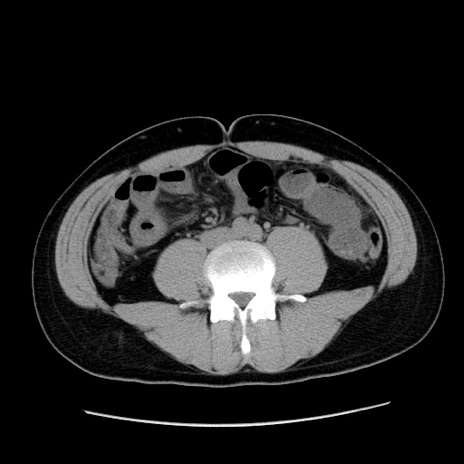

冠状断像

【症例】20歳代 男性

【主訴】心窩部痛

【現病歴】今朝より上腹部痛あり。一旦軽快していたが再度出現したため救急要請。昨日夕に白身の魚を含む刺身を食べた。

【身体所見】BP 136/89mmHg、HR 74/min、BT 37.0℃、腹部:膨満、軟、心窩部に圧痛あり。反跳痛なし、筋性防御なし、腸雑音やや亢進あり。

【データ】WBC 17700、CRP 0.48